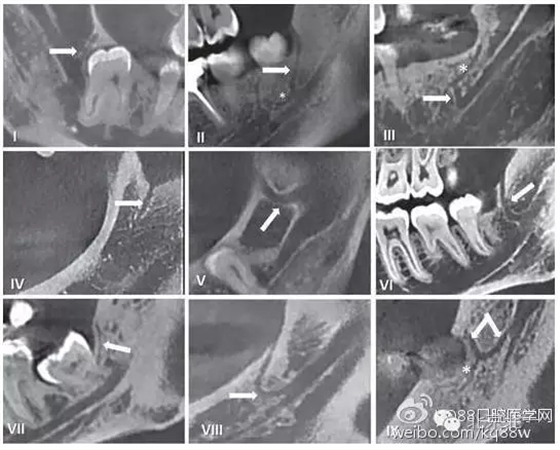

圖三 磨牙后管三種走行方向示意圖:

Type A.垂直走行;Type B.斜向走行;Type C.水平走行。

在臨床工作中,個(gè)體解剖差異導(dǎo)致像磨牙后管這類的神經(jīng)分叉及神經(jīng)走行的變化,術(shù)前只能通過放射方法檢測(cè)。但使用口腔曲面斷層片之類的常規(guī)二維影像學(xué)照片是難以檢查到的。隨著現(xiàn)代醫(yī)學(xué)影像技術(shù)的發(fā)展,出現(xiàn)了計(jì)算機(jī)斷層掃描(CT)和錐束CT(CBCT),其在口腔醫(yī)學(xué)領(lǐng)域的成功運(yùn)用使得磨牙后管的術(shù)前影像評(píng)估成為可能。精確的捕捉到下頜磨牙后管的解剖走行,需要高分辨率的成像設(shè)備并保證攝像期間患者沒有晃動(dòng)。下面我們將用幾張CBCT影像圖片為大家圖示說明。

640.webp (4).jpg

圖五 使用CBCT拍攝到的不同走行的下頜后管

通過對(duì)磨牙后三角(RMT),磨牙后孔(RMF)和磨牙后管(RMC)解剖學(xué)結(jié)構(gòu)及其臨床走行的認(rèn)識(shí),將會(huì)幫助我們?cè)谂R床工作中,進(jìn)一步減少磨牙后區(qū)操作所造成的意外損傷。